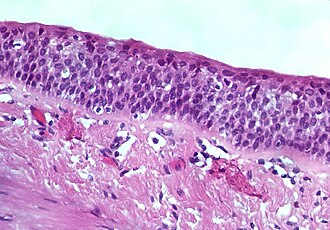

Bronchial squamous metaplasia. H&E stain.

Squamous metaplasia, abbreviated SM, is a benign transformation of an epithelium to a squamous morphology.